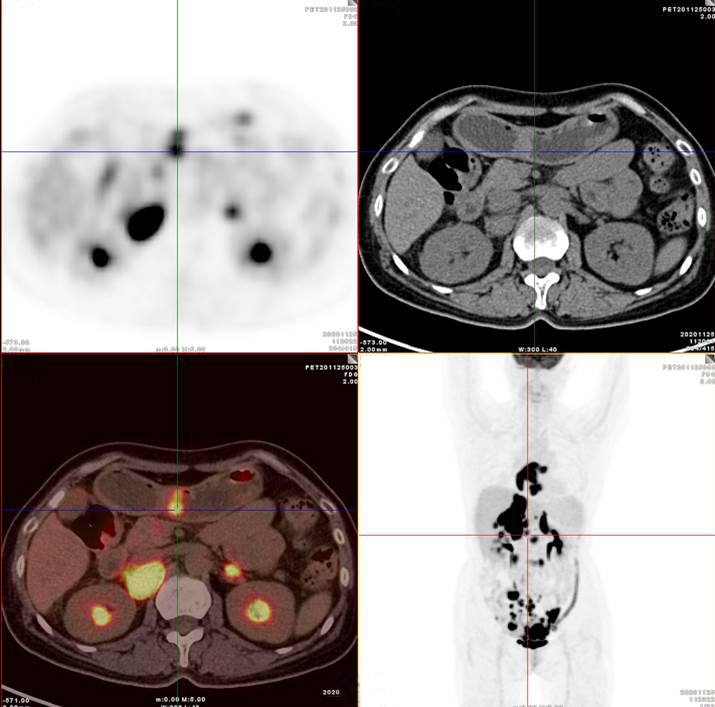

雙側(cè)腎上腺病灶、腹膜后淋巴結(jié)放射性攝取明顯增高

膽囊及雙腎上腺病灶、腹膜后淋巴結(jié)放射性攝取明顯增高

胃、雙腎上腺病灶、腹膜后淋巴結(jié)放射性攝取明顯增高

腸系膜多發(fā)淋巴結(jié)放射性攝取增高

左/右心房壁增厚、雙側(cè)腎上腺腫塊、膽囊壁結(jié)節(jié)、胃竇壁結(jié)節(jié)及多段小腸腸壁增厚,上述代謝不同程度明顯增高;腹膜后、腸系膜多發(fā)高代謝淋巴結(jié)。

考慮淋巴瘤,請結(jié)合臨床病理